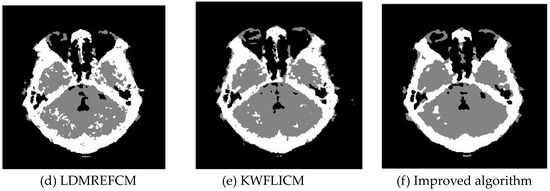

Multiplicative noise was added to the remote sensing image, the medical image, and the man-made image with a mean value of 0 and mean variances of 80, 114, 140, and 161. The number of clusters was set to 3, 4, 2, and 2. The experimental results are shown in Figure 10, Figure 11, Figure 12 and Figure 13. The error rate of the segmentation results is shown in Table 7 and Table 8. The iteration times and number of iterations of the algorithms are shown in Table 9 [46,47,48].

3.3.2. Test Result

Comparing the results of the image segmentation with multiplicative noise in Figure 10, Figure 11, Figure 12 and Figure 13, we can see that the FCM_S and FLICM algorithms took neighborhood information into account and suppressed part of the multiplicative noise. The KWFLICM and LDMREFCM algorithms could remove a large number of noise points. Compared with the other algorithms, the improved algorithm contained the fewest noise points. The edges of the segmentation results were continuous and smooth [49]. Compared with Table 7, the PSNR of the improved algorithm was the largest, which proved that the improved algorithm had a better robustness against multiplicative noise. Comparing the error rate of the segmentation results of each algorithm in Table 8 shows that the segmentation results of this algorithm were closer to the ideal segmentation results and had a better segmentation performance. Combined with the comparison of the iteration times in Table 9, the segmentation performance and PSNR of the KWFLICM algorithm were lower than those of the improved algorithm, and the iteration time of the improved algorithm was much shorter than that of the KWFLICM algorithm. In conclusion, the improved algorithm not only guaranteed good robustness against noise, but also reduced the iteration time and improved the operation efficiency of the algorithm.

Figure 12. Multiplicative noise disturbing brain CT images (a) and the segmentation results (bf).

Sensors 20 02391 g012aSensors 20 02391 g012b